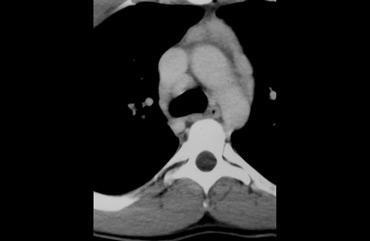

Hãy mô tả hình ảnh bên trái.

Sau đó tiếp tục.

CT cho thấy một khối nằm ở trung thất trước.

Khối có dạng nang nhưng có các thành phần đặc ngấm thuốc cản quang, do đó cần lo ngại đến u lympho, u tế bào mầm và u tuyến ức dạng nang.

Trường hợp này được xác định là u tuyến ức dạng nang.